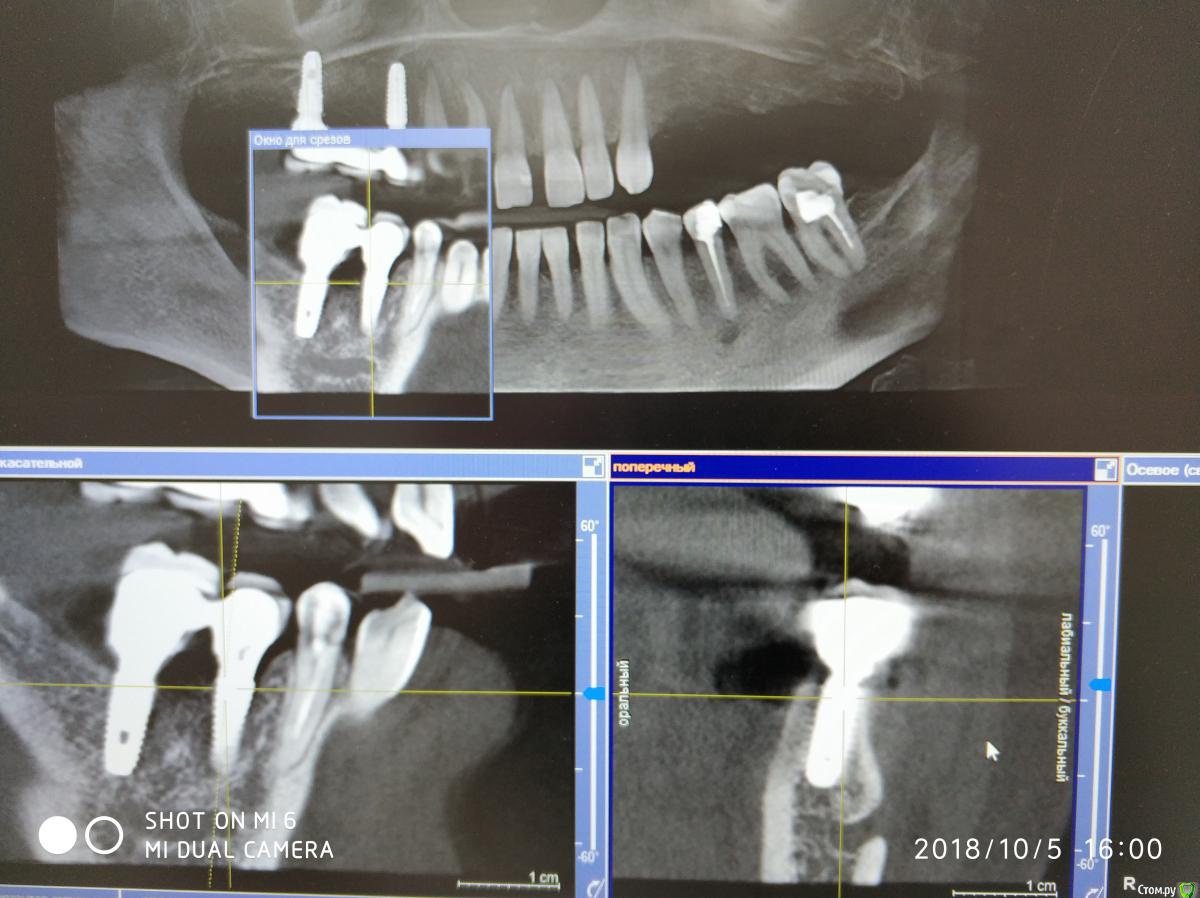

Nazim_NV86 Опубликовано 11 октября, 2018 Автор Поделиться Опубликовано 11 октября, 2018 Появилась свежая КЛКТ Ссылка на комментарий

Nazim_NV86 Опубликовано 11 октября, 2018 Автор Поделиться Опубликовано 11 октября, 2018 (изменено) Женщина. Примерно 50-53. Скрины синуса сделал, но замотался и забыл выложить. Синусы вч оба чистые. Слева правда есть маленькое мукоцеле. Сегодня предложил ей снять коронки и походить с формирователями. По семейным причинам уехала к дочери помогать. Отложили на месяц. Так у нас есть месяц на расследование ) Изменено 11 октября, 2018 пользователем Nazim_NV86 Ссылка на комментарий

Nazim_NV86 Опубликовано 12 октября, 2018 Автор Поделиться Опубликовано 12 октября, 2018 Срезы пазух. На чувствительность языка жалоб не слышал. Как приедет тесты сделаю. Ссылка на комментарий